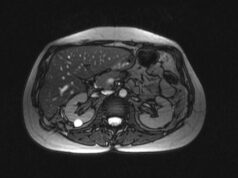

(специальные растворы, диета за 24 часа). - Принесите результаты предыдущих обследований: УЗИ, МРТ, анализы кала.

- Инструментальные процедуры: аноскопия, сигмоидоскопия, колоноскопия.